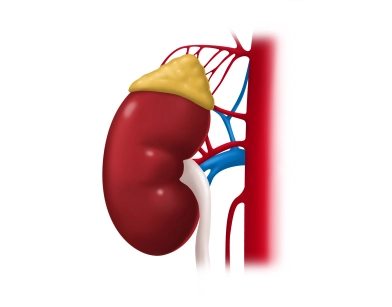

Lehrbeiträge aus den Bereichen der Allgemein- und Viszeralchirurgie, Gefässchirurgie, Gynäkologie, Thoraxchirurgie, Robotik und Handchirurgie Schritt für Schritt in Videos erklärt.